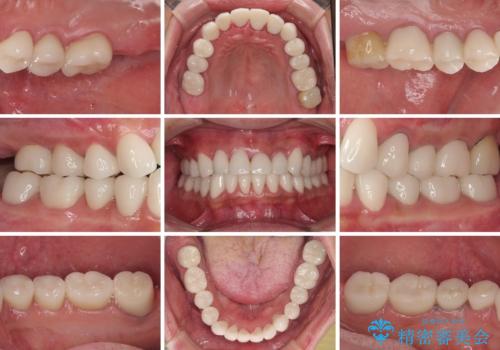

当初はむし歯処置が必要な歯のみの治療予定でしたが、捻転や咬み合わせを可及的に改善したいとのことで、全顎的にオールセラミッククラウンにて補綴治療を行うこととしました。

反対咬合を補綴治療で改善すると、上唇へ歯が当たる感覚や、発音時の舌感覚が急激に大きく変化するため、違和感になれるまで時間を要することになります。

仮歯で過ごす期間を一定期間も受けることで徐々に変化になれていくようにし、オールセラミッククラウン装着時には違和感なく過ごすことができるようにしています。